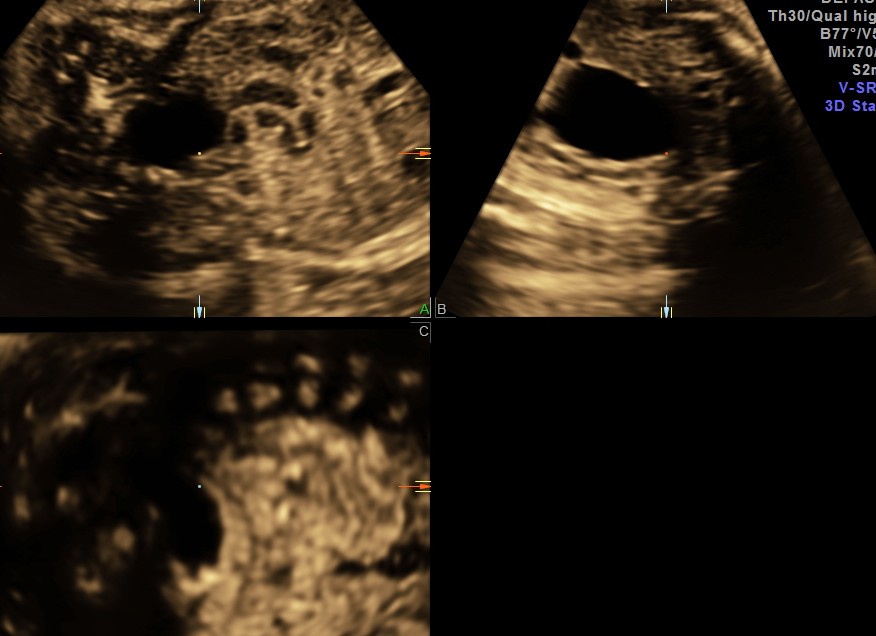

The following images show bilateral renal pelvi ectasis and bilateral dilated ureters with all the changes more in the left kidney .

The left kidney also showed possible duple-ix pelvis with double ureters arising from them . But this finding could not be confirmed in all the views .